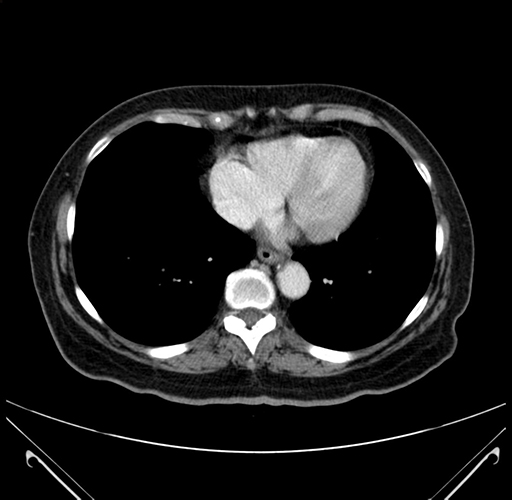

Axial Venous